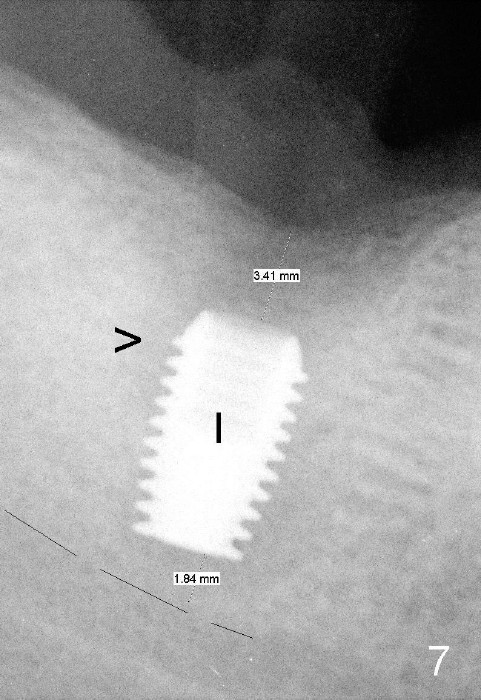

It is advantageous to place implant immediately or shortly (4-8 weeks) after extraction.  But most teeth to be extracted are potentially infected, such as in the case of Ms. Pei (Fig.1).  Periapical radiolucency (PARL) is not obvious prior to extraction. Six weeks post-extraction, osteotomy is finished with bone expansion and drilling (Fig.2 D, 5x14mm).  Tatum tapered implant is placed (Fig.3 I: 6x14). So far PARL is minimal if any (Fig.2,3 <).  Pain develops approximately 20 days post-implantation with expanding PARL (Fig.4 <).  Antibiotic treatment does not resolve the infection.  The implant has to be removed.  Infected granulation tissue is thoroughly removed from the apical portion of  the socket (Fig.5 <) with a curette (C).  Scaling and root planing is done for 4 quadrants.  A month later, potentially infected hard tissue is removed by reamers (Fig.6 D, 5 mm).  Bicon implant is buried inside the bone and separated from the oral cavity (Fig.7 I, 5x8).  At that time, there is a gap next to the implant (>).  Five months later, the gap disappears, suggesting implant osteointegration (Fig.8).  Extraoral cementation is done between abutment (A) and crown (C).  The abutment/crown unit is tapped into the implant with 2 visible threads (<).  The latter indicates that the abutment is completely seated.  Dashed lines in Fig.5-7 denote the upper border of the inferior alveolar canal.  PAs are taken 6 months (Fig.9) and 1 year 7 months (Fig.10) post cementation.  In all, it is a hassle to do re-implantation.  Efforts should be exerted to prevent post-implant infection.